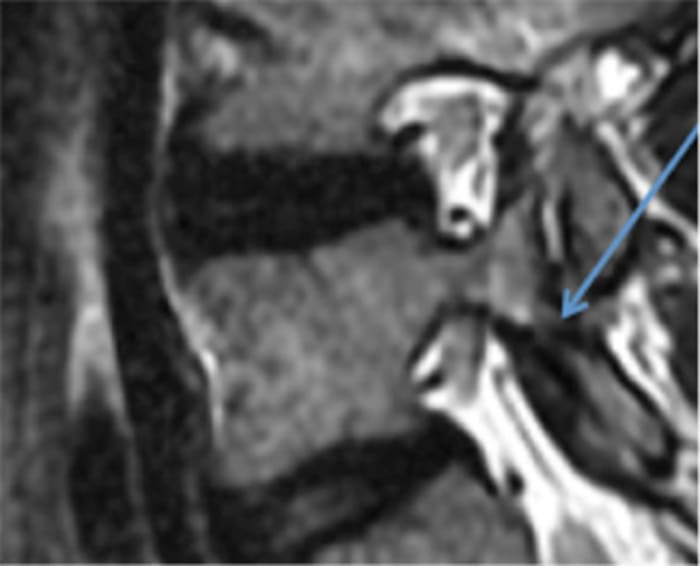

One of the most common lumbar spine injuries seen in athletes is a stress fracture (spondylolysis) of a small bone (the pars interarticularis) in the posterior aspect of the low back (Figure 1). While this injury most commonly occurs during adolescence, some patients will not develop symptoms until adulthood. It commonly occurs in athletes who repeatedly hyperextend (excessively arch) their low back, such as gymnasts and football players (particularly offensive linemen). However, this injury has been reported in athletes in all sports. The condition recently received widespread attention when it forced Joel Embiid to miss the 2014 NCAA college basketball tournament. Additionally, a patient’s specific pelvis and lumbar spine anatomy may increase the risk of developing this injury.

Repeated hyperextension may lead to impingement of the bony elements in the posterior lumbar spine, and while this minor trauma is not sufficient to cause a fracture in isolation, when it is repeated over and over again, eventually the bone will break. Imagine a paper clip: You can bend the paper clip many times, and it won’t break; but if you bend it one too many times, the entire thing will snap.